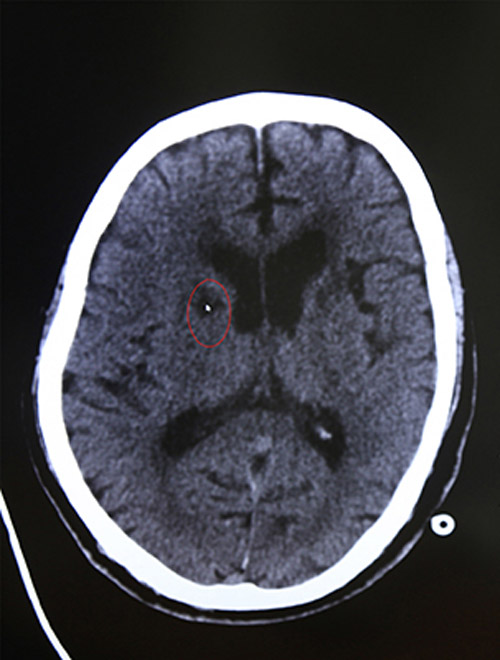

急诊CT示:排除脑出血

颅脑MRI示:右侧基底节区脑梗塞

16:44 影像科3分钟出报告,CT报告显示:排除脑出血。为进一步查看脑血管情况,又迅速完成了颅脑血管磁共振检查,结果显示:脑梗塞。

(结合影像学检查,了解到老人有脑梗发病史,李振并主任判断患者系急性脑梗,发病时间为15:30,还处于静脉溶栓治疗3小时的时间窗内,有溶栓治疗指征,可溶栓治疗,积极治疗血管有再通希望。)